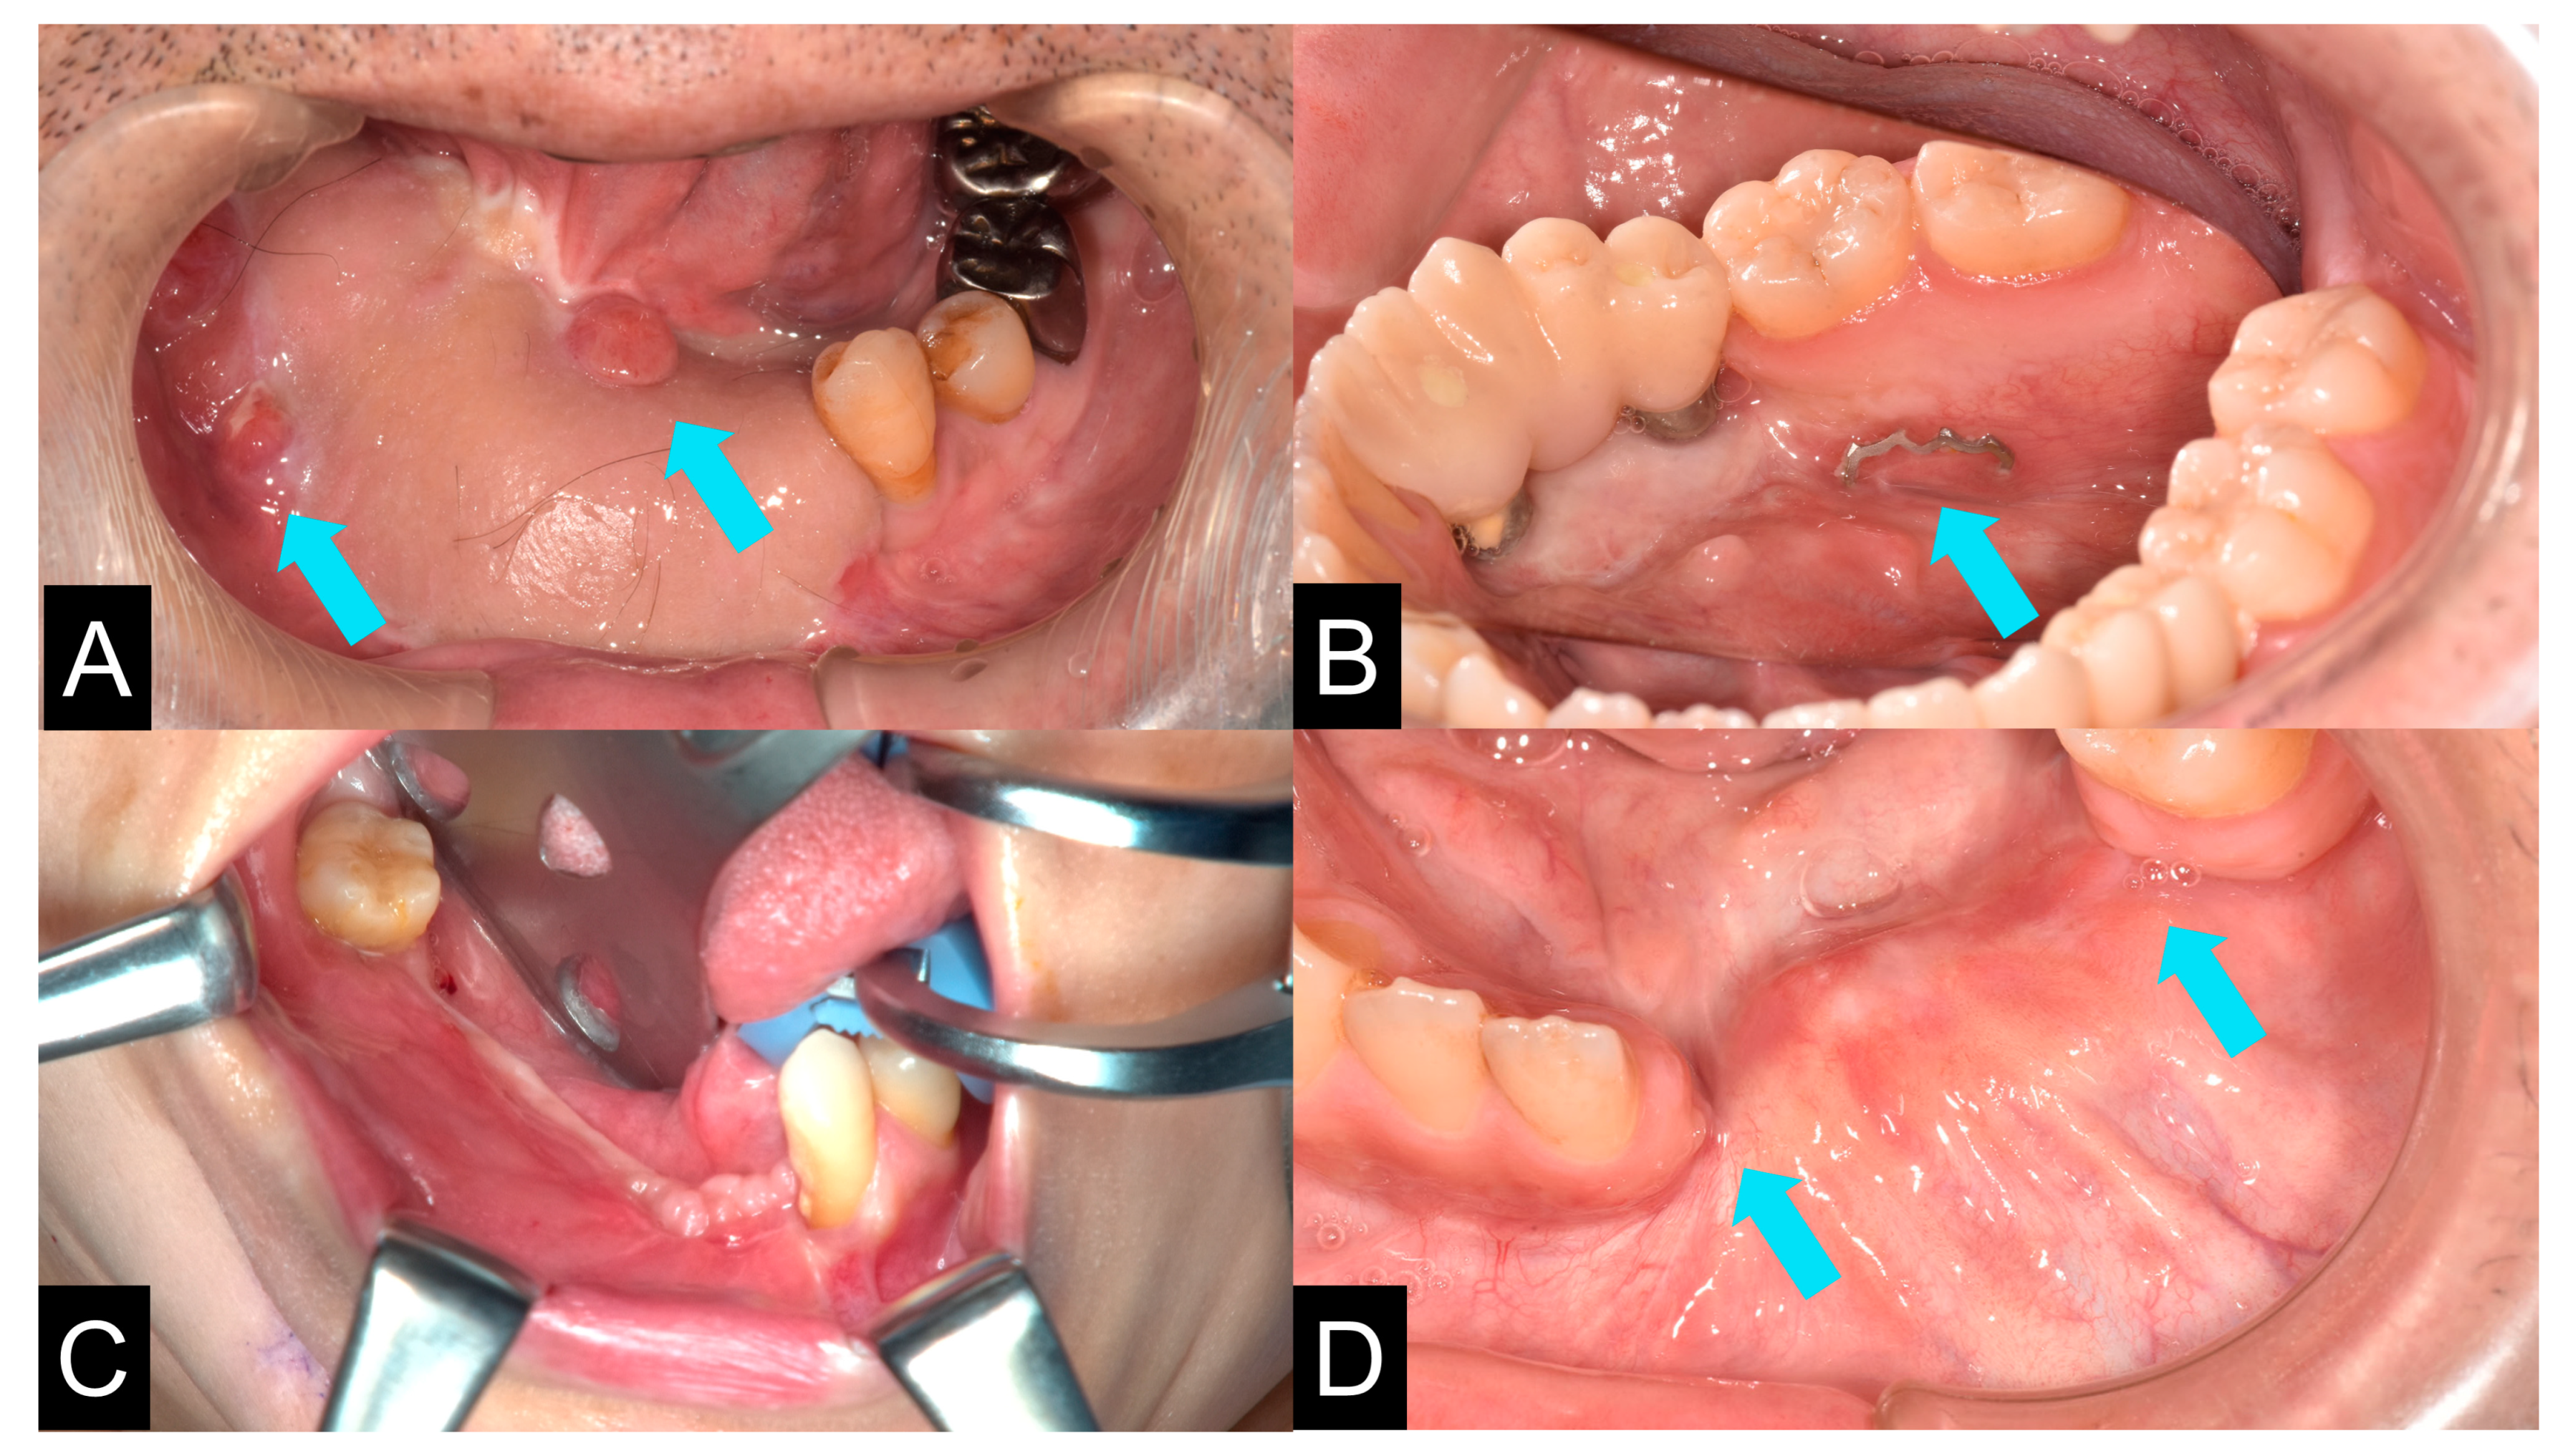

| Case | Gender | Age | Diagnosis of Primary Disease | Primary Reconstruction | Bone Defect | Classification Of Js Brown | Schematic of Mandibular Defect |

|---|---|---|---|---|---|---|---|

| 1 | M | 23 | Ameloblastic carcinoma | None | Marginal bone defects | Marginal bone defect | ![]() |

| 2 | M | 73 | SCC Gingiva | Surgical plate | Segmental bone defects | Body-chin Class II | ![]() |

| 3 | F | 78 | SCC Floor of mouth | Rectus abdominis musculocutaneous flap and surgical plate | Segmental bone defects | Body-chin Class III | ![]() |

| 4 | M | 70 | SCC Floor of mouth | Anterior cervical flap | Marginal bone defects | Marginal bone defect | ![]() |

| 5 | F | 69 | SCC Gingiva | Surgical plate | Segmental bone defects | Ramus-body Class I | ![]() |

| 6 | M | 69 | Osteoblastoma of the mandible | None | Marginal bone defects | Marginal bone defect | ![]() |

| 7 | M | 73 | SCC Gingiva | None | Marginal bone defects | Marginal bone defect | ![]() |

| 8 | M | 69 | Ameloblastoma | Simultaneous surgery | Segmental bone defects | Ramus-body Class I | ![]() |

| 9 | M | 58 | Mucoepidermoid carcinoma Floor of mouth | Vascularized fibular bone graft | Segmental bone defects | Ramus-body-chin Class III | ![]() |

| 10 | M | 60 | Ameloblastoma | Fractured surgical plate | Segmental bone defects | Ramus-body Class I | ![]() |

| 11 | F | 62 | SCC Gingiva | Fractured surgical plate | Segmental bone defects | Ramus-body Class II | ![]() |

| 12 | M | 81 | SCC Gingiva | None | Marginal bone defects | Marginal bone defect | ![]() |

| 13 | F | 50 | Odontogenic myxoma | Surgical plate | Segmental bone defects | Body-chin Class II | ![]() |

| 14 | M | 74 | SCC Gingiva | Surgical plate | Segmental bone defects | Body-chin Class III | ![]() |

| 15 | M | 62 | SCC Gingiva | Vascularized scapular bone graft (non-union) | Segmental bone defects | Body-chin Class I | ![]() |

| 16 | F | 45 | Ameloblastoma | Surgical plate | Segmental bone defects | Ramus-body Class I | ![]() |

| 17 | M | 17 | Ossifying fibroma | None | Mandibular partial resection | Marginal bone defect | ![]() |

| 18 | M | 63 | Ameloblastoma | Fractured surgical plate | Segmental bone defects | Ramus-body-chin Class III | ![]() |